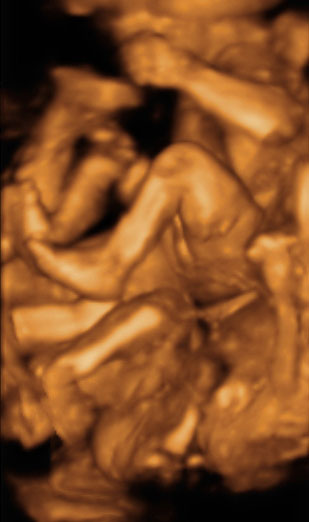

Ecografía 3D de la semana 20: Embarazo de trillizos

La ecografía en 3D de un embarazo de trillizos en la semana 20 puede resultar complicada de interpretar: piernas y brazos de los pequeños se confunden. Los fetos tienen poco espacio dentro del útero materno.

Uno de los bebés está cabeza arriba y los dos hermanos se disputan el espacio inferior del útero. Los brazos y piernas se entremezclan en esta ecografía, que exige una gran concentración por parte de especialista. El ginecólogo que tiene que "aislar" tres fetos dentro de un mismo útero. En estos casos, el examen ecográfico dura más tiempo para verificar el buen estado de todos los fetos.